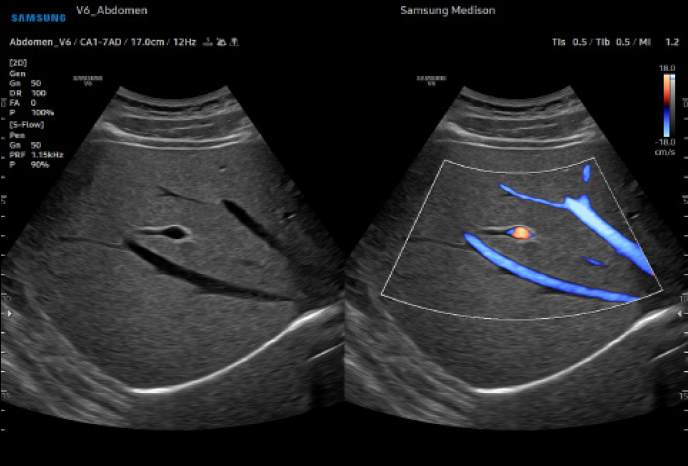

Samsung V6 Ultrasonic

고급 도플러 기능으로 심혈관 평가 및 이상 감지

심장심장의 해부학 구조 및 혈류역학적 평가, 순환기계 장애, 심장 수축·이완

미세혈류 플로우

루미플로우

S-플로우